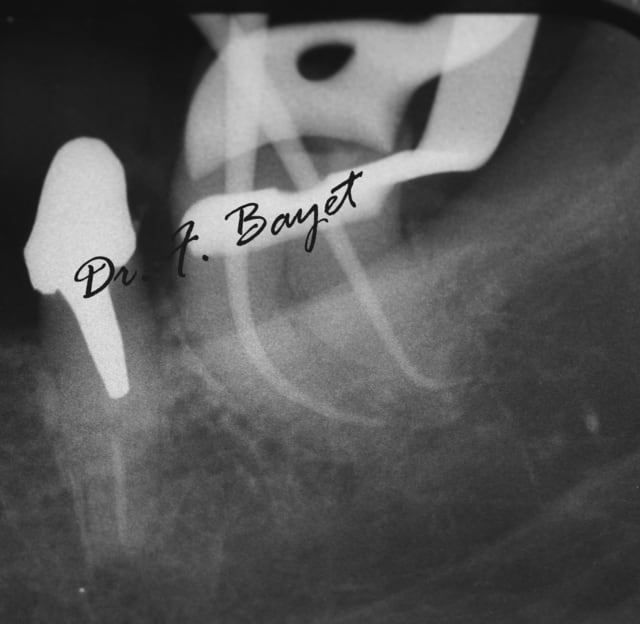

Exemple: sur une 38, cathétérisme au PathFile (violet, blanc, jaune) et WaveOne (toujours avec l'ATR), obturation systemB. Le crochet apical je l'ai découvert au moment de l'essayage des cônes !!

Img 0753  copie ugylxo - Eugenol

Img 0755  copie vongmr - Eugenol

Img 0759  copie tor4et - Eugenol